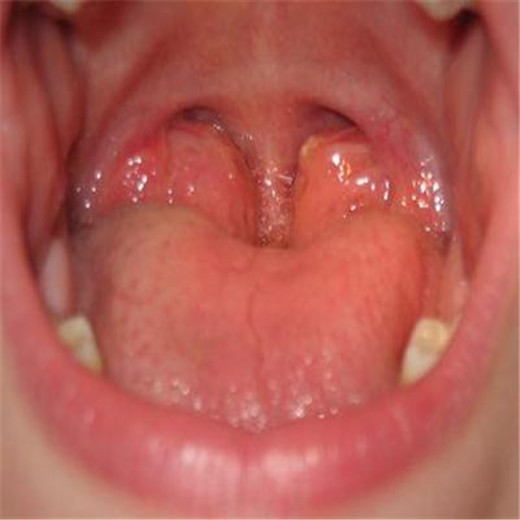

扁桃體炎圖片

扁桃體腫大